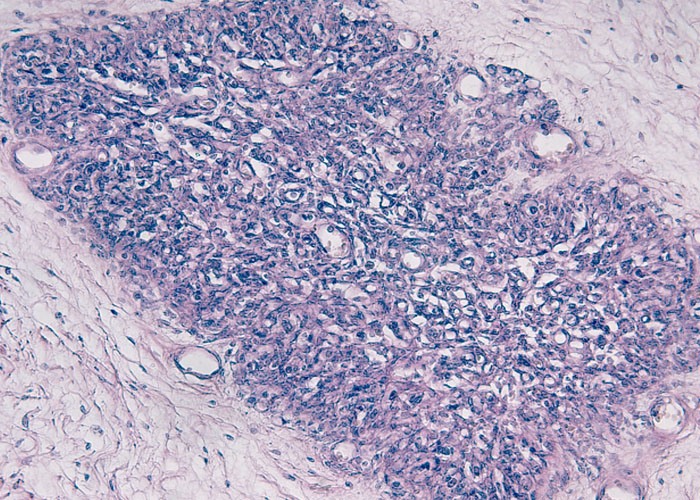

На ультразвуковых исследованиях вилочковой железы отмечается значительное уменьшение массы или даже полное отсутствие органа (агенезия). ЭхоКГ и другие кардиологические методы диагностики выявляют многочисленные пороки сердца (например, дефект межжелудочковой перегородки) и сосудов средостения. Иммунологические исследования подтверждают значительное падение уровня Т-лимфоцитов. Это же явление наблюдается в периферической крови и нередко сочетается с уменьшением концентрации белков-иммуноглобулинов. Биохимическое изучение крови свидетельствует о снижении уровня кальция и гормонов паращитовидной железы. Врач-генетик может выполнить поиск делеций в 22-й хромосоме посредством флуоресцентной гибридизации ДНК или мультиплексной полимеразной цепной реакции.